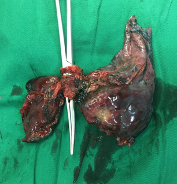

常规腔镜方面,以胸部肿瘤外科为主,开展肺叶、肺段、复合肺段/亚段切除、解剖性肺切除、袖状切除等手术,包括单孔到多孔等各种入路。在北京市较早开展微创食管癌切除,积累了丰富的经验。纵隔肿瘤方面,开展包括剑突下及其他入路胸腺切除、胸腺扩大切除,无名静脉成型等。同时结合锚丝定位、术前三维重建技术和荧光腔镜技术使手术安全高效。